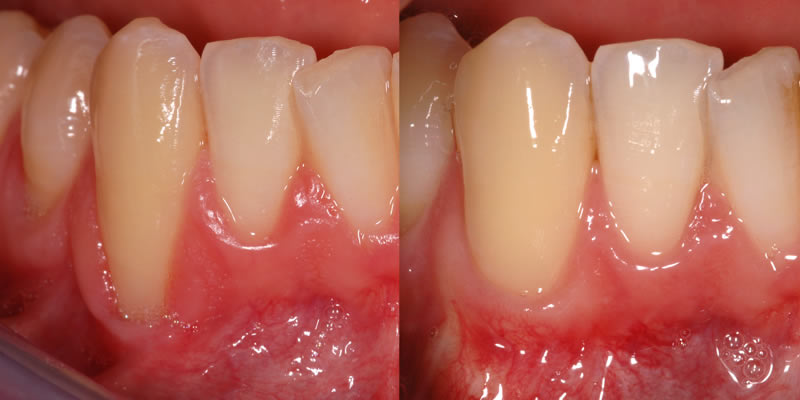

Periodontal Plastic Surgery Procedures

Periodontists are often considered the plastic surgeons of dentistry. If you are looking to improve your smile, a periodontist may be able to help.